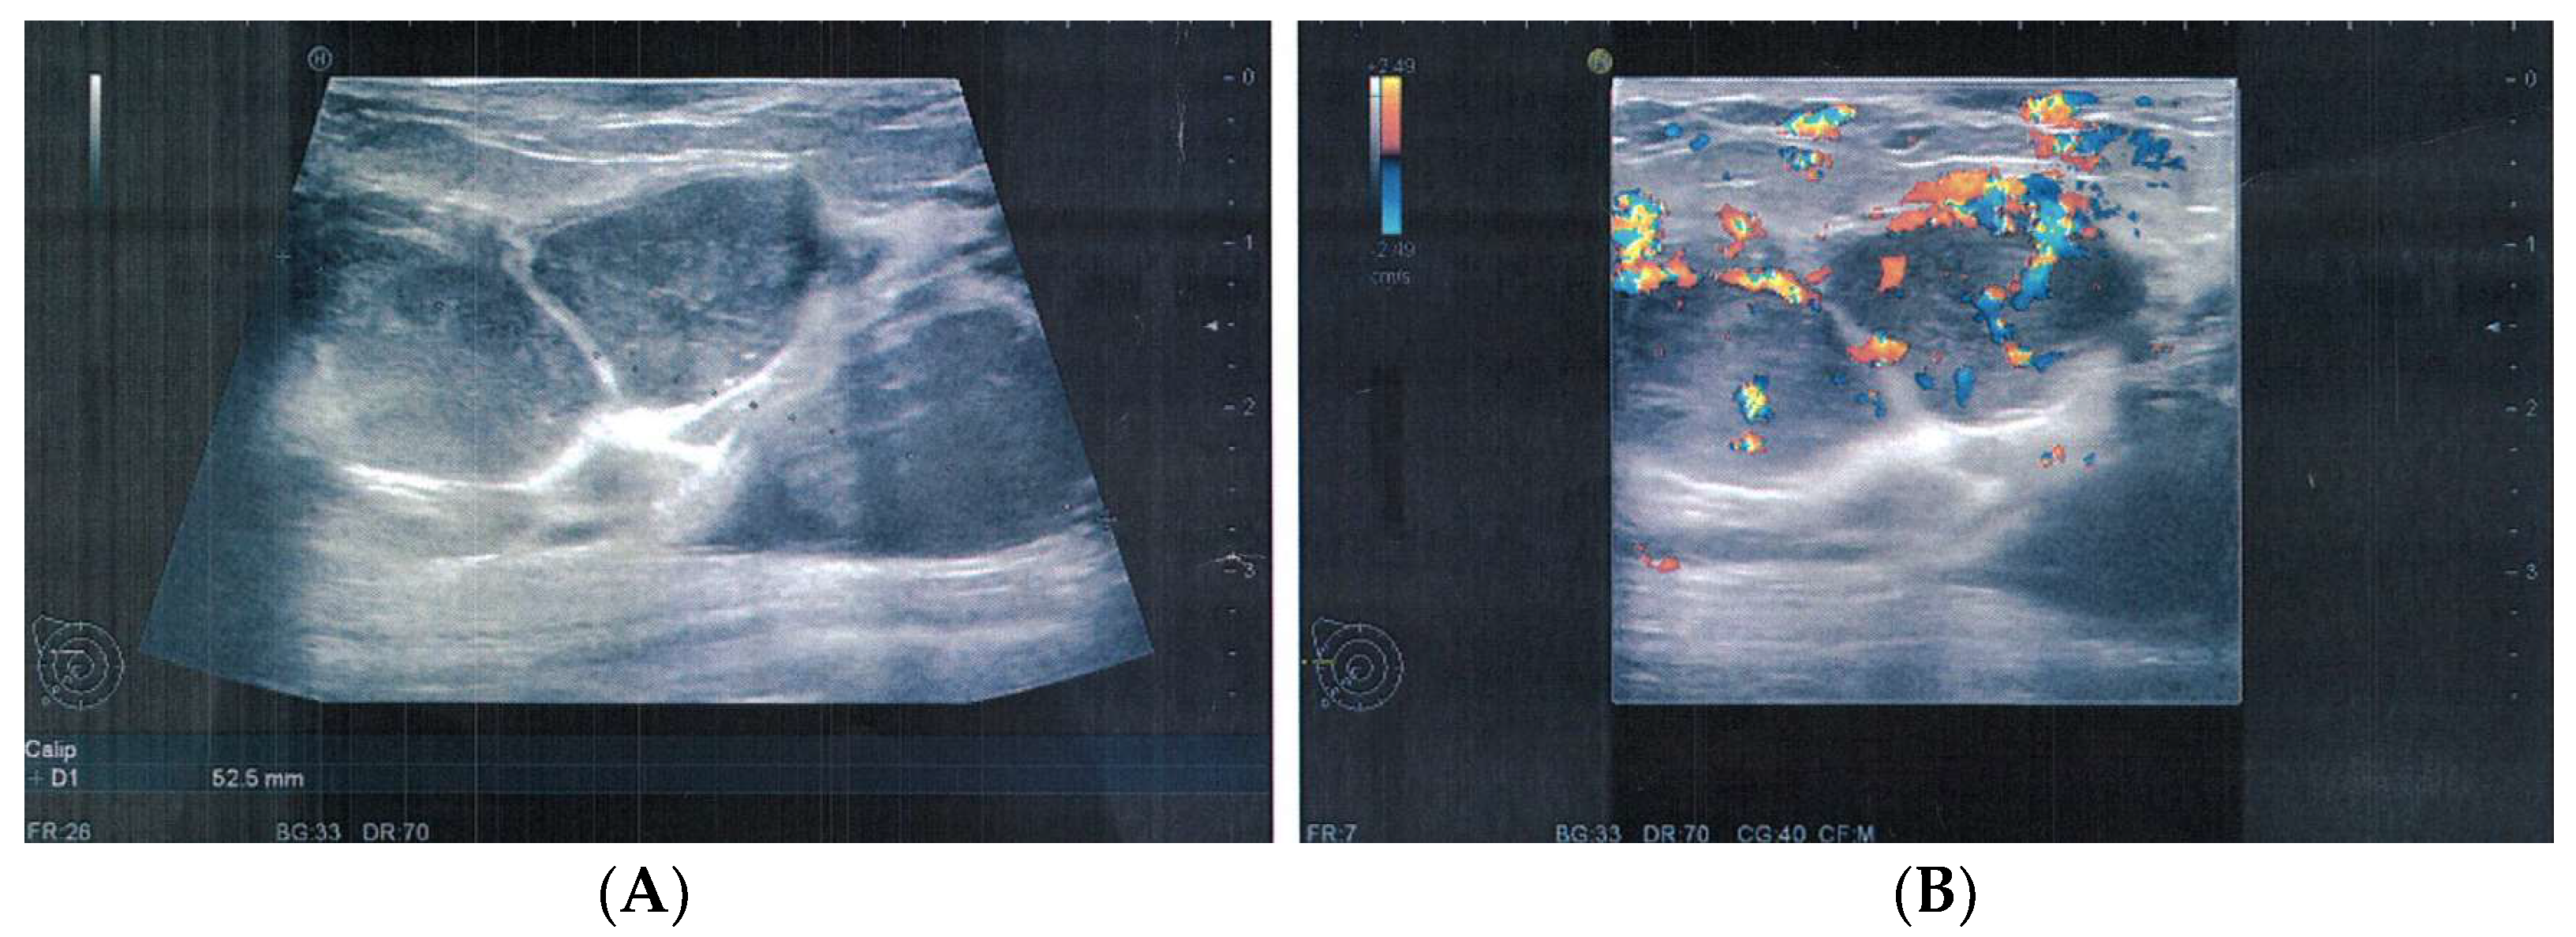

2. Case Presentation